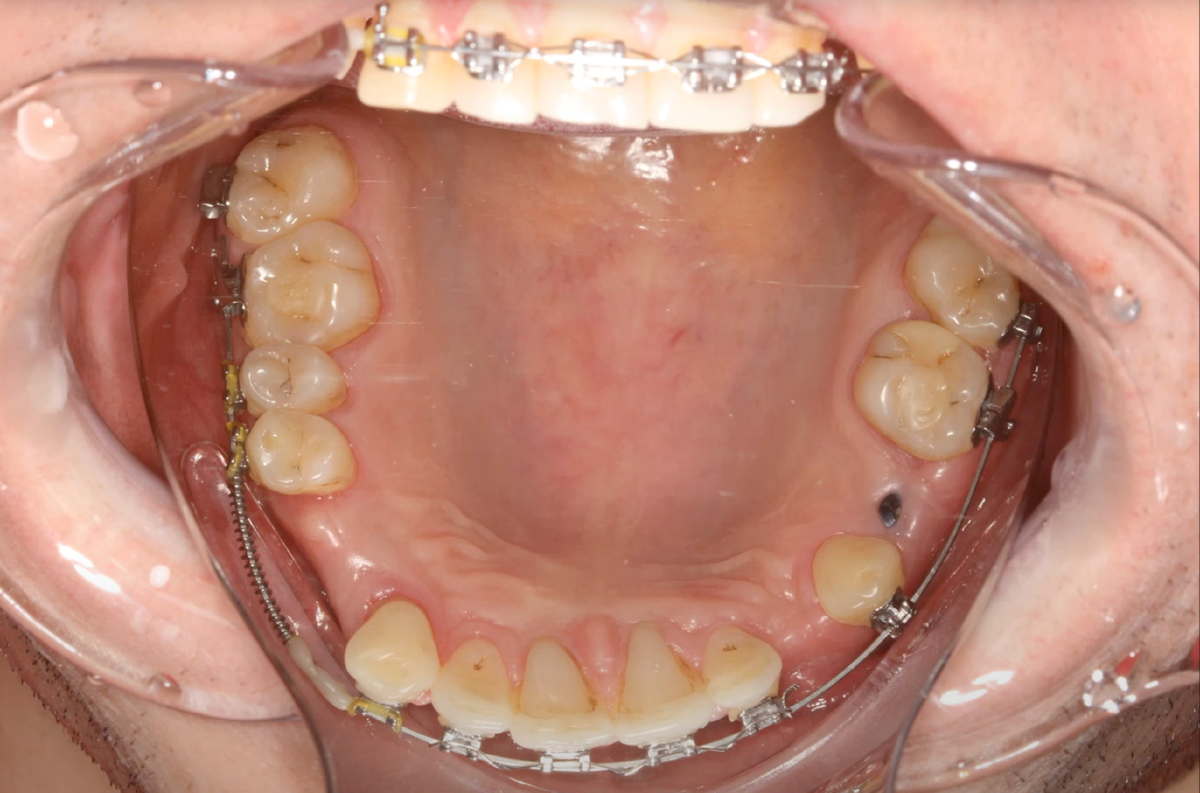

На нижней челюсти созданы промежутки, но для чего — тоже неясно. Складывалось ощущение, что врач собирался поставить «большой» зуб туда, где должен быть небольшой премоляр. В итоге получилось явное несоответствие размеров верхних и нижних зубов.

Нижняя челюсть пациента